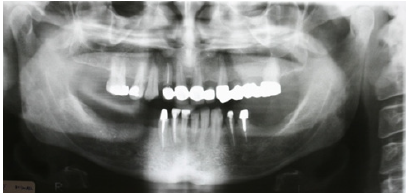

Figure 2: Preoperative panoramic radiograph.

The patient reported a free medical history, but admitted smoking habit (20+cig/day). He was not taking any medication and reported pain in facial muscles during stressful periods. The patient was subjected to thorough clinical and radiographic examination (panoramic x-ray) (Figure 2). Intraorally, he presented severe abrasion most observed in mandibulary dentition, reduced VDO, and several missing mandibular teeth (#44,45,46,47 and 36,37). In the maxilla, a 4-unit metal ceramic bridge with a cantilever was found on the incisors {12-11-21-(22)}, and one 4-unit metal-acrylic bridge in the posterior segment {23-(24)-(26)-27}. The visible diastemmas between #12,#13 and #13,#14 were due to a missing premolar #15 which probably caused distal migration of #14 and 13 (Figure 3-5). The smile line was evaluated as medium (Figure 6). Secondary caries was visible in amalgam restorations in #14 and #16 and was inspected under the abutment #12. A significant change in the occlusal plane was obvious, defined by significant protrusion of #13, #14 and #16. In the mandible acrylic crowns were positioned in #44, 33, 34. Initial radiographic examination revealed endodontic therapies in #12, 34, 35, 42 and #43 and it was estimated that the bone level averaged at 70%. Clinical examination of the stomatognathic system revealed bilateral myalgia of the lateral pterygoid muscles on palpation, unilateral clicking on the left TMJ and limitation in mouth opening. All other masseter muscles were free of symptoms.